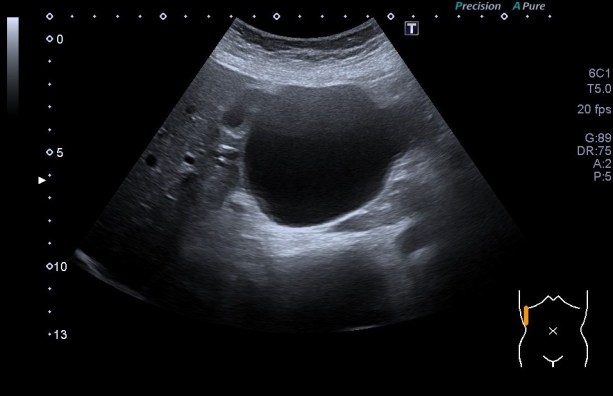

La imagen que debes de conseguir en una imagen normal del hígado es el en lóbulo hepático derecho y sería esta:

La imagen típica de hepatopatía crónica sería esta:

Puedes observar la superficie hepática en forma de olas y la heteroecogenicidad del hígado..

Compara la dos imágenes y percibe los cambios, así podrás reconocer siempre estos cambios.